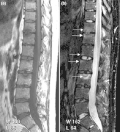

Approximately 25–70% of PsA patients have inflammation of the axial skeleton.[12] There are also post inflammatory changes.[1] Axial pain can occur in the area of the sacrum (the lower back, above the tailbone),[7] as a result of sacroiliitis or spondylitis, which is present in 40% of cases. The inflammatory pain in the axial skeleton is worse in the early hours of the day.[1] The pain is not relieved by resting, but rather by movement.[1] The pain may be located in only part of the spine or sacroiliac joints, and may radiate to the legs down to the level of the back of the knee.[1] It may be on both sides or only one side. There may also be stiffness and reduction of mobility in the spine. There are no symptoms in 20% of people with axial involvement.[1] Over time, the spine may undergo ankylosis.[1]